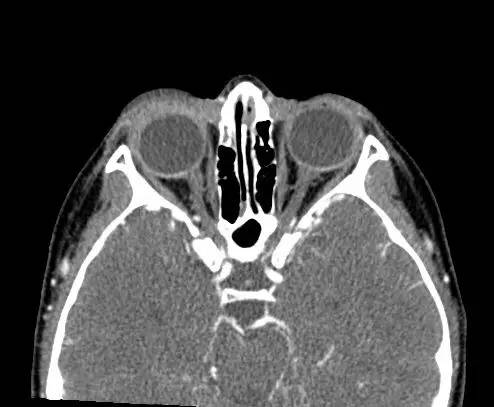

右侧上眼睑软组织肿胀。上眼睑与眼球间可见矩形积气,约1 cmx 0.4 cm x 0.4 cm,并线样影在内穿行。眼球及晶状体正常。眶隔后及眶内软组织无肿胀、血肿或脂肪条纹提示为创伤性。无对比剂外渗。无对急性骨异常。右侧上颌窦粘膜增厚。

【诊断】右上眼睑和眼球间木片存留

There is a piece ofwood between the superior right eyelid and the globe.